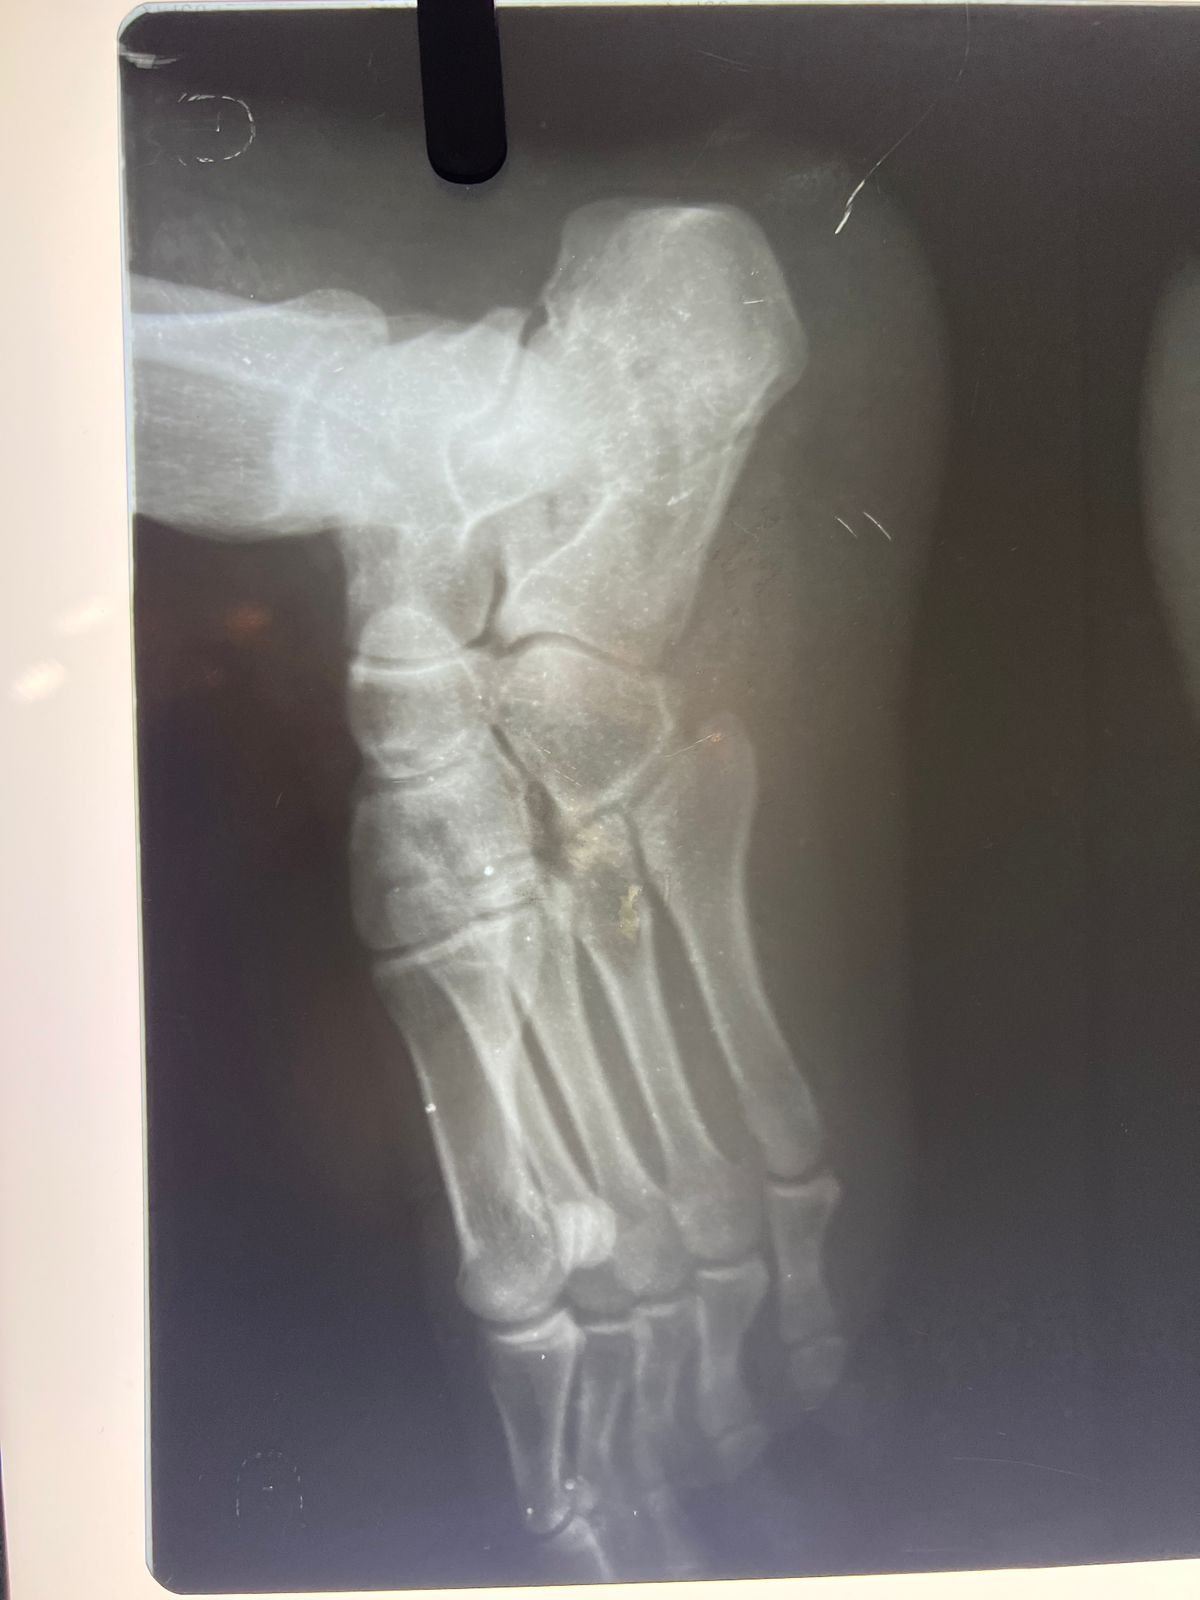

& fibula | Heal fracture pre & postop | Clavicle

fracture pre &

postop | Congenital foot deformity pre & post

Heal fracture pre & postop | Clavicle fracture pre &